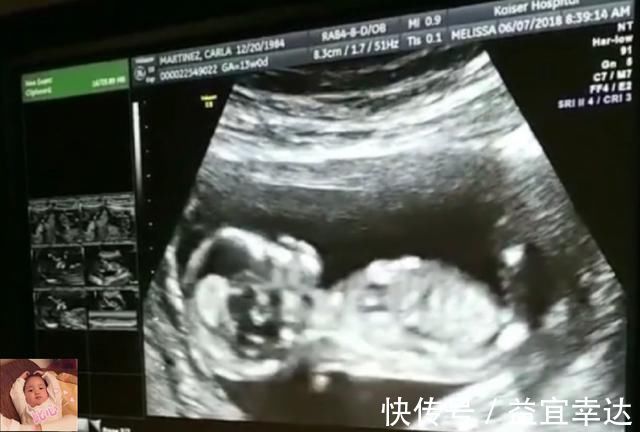

早上伴随着孕妈的起床,16周以后的胎宝宝也会被充足的光线所叫醒的,睁开眼睛,看向有光亮的地方,胎宝宝也正式起床啦。

胎宝宝不需要刷牙洗脸,所以起床后,6周左右的胎宝宝就会做个晨练,像一条小鱼一条,在妈妈的肚子里游来游去。

但28周后的胎宝宝因为体型的限制,只能放弃这项最爱的运动了。